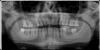

Doc Опубликовано 30 декабря, 2008 Поделиться Опубликовано 30 декабря, 2008 Уважаемые доктора, подскажите пожалуйста что можно сделать в моей ситуации?Верхний зуб с правой стороны удален лет 5 назад, нижняя 6рка - 2месяца назад. На консультации сказали что парадонтит и требуется парадонтологическое лечение и еще ряд зубов скорее всего пойдет на удаление. Прежде чем идти "под гильотину" хотел бы получить независимое мнение , какие зубы еще можно спасти, какие точно требуют удаления.Если зуб по ощущениям прочно сидит и не шатается, можно ли его не удалять, а вылечить? Можно ли начать какие-то действия по имплантации (например, наращивание кости или постановку имплантанта в нижнюю 6-рку) одновременно с парадонтологическим лечением или нужно сначала закончить с парадонтологией, а потом уже только приступать к имплантации? Сходил на консультацию к имплантологу в клинику рядом с домом. Он после 5минутного осмотра написал в плане лечения одним из пунктов "Сложное удаление" 4 зубов. Чем оно отличается от простого и нужно ли в моем случае именно сложное удаление, или это просто "развод на деньги"? С финансами проблем нет, готов ставить Replace, но хотел бы по возможности не удалять зубы если их можно вылечить. Все же родные зубы лучше любых имплантов. Извините за большое количество вопросов. Буду очень признателен за ответы и за рекомендацию хорошего имплантолога и парадонтолога в СПб. В Вашем случае по одному снимку не сказать сколько там еще пойдет под удаление и т.д. Нужно щупать, двигать, прикусывать и смотреть в реальности. Здесь давать рекомендации нельзя, может быть кто-то напишет в личку, либо читайте форум и ищите питерских стоматологов. Ссылка на комментарий